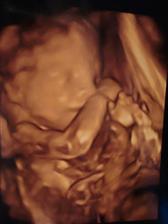

Tak dnes sme s budúcim tatinkom boli v slávnom Gennete a obaja sme odtiaĺ odchádzali s nadšením,pán docent bol skvleý,veĺký profesionál a odborník a hlavne nás ubezpečil,že malý je v poriadku a už teraz je to poriadny chlapisko 🙂

tak už máme vybraný a skoro objednaný kočiarik pre princa,už nám chýba len postieĺka a nejaké drobnosti,ale na to máme ešte čas 🙂